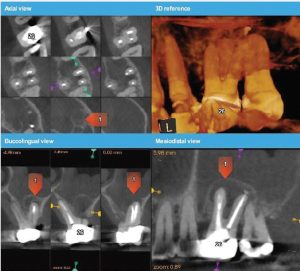

The patient was referred for a CBCT; the scan (Figure 5)

revealed a common area of rarefying osteitis surrounding the mesial buccal and distal buccal roots which had caused elevation of the sinus floor. As the endodontic pathology had not resolved, treatment options were proposed. The patient chose to have microsurgical therapy performed.

A JD–printed stereolithographic template was created by combining the CBCT scan data with an intraoral scan’s (3Shape Trios intraoral scanner) digital data. The data was then imported into Codiagnostix software in order to plan our approach and design our cortical window dimensions for optima l access to the roots (Figure 6).

The guided microsurgical approach would facilitate an osteotomy design to minimise the potential for sinus membrane perforation. The JD-printed guide for the cortical window would guide the length and angle of the osteotomies using the piezosurgical saw (Figure 7).